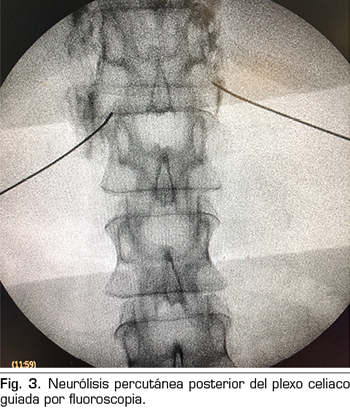

– Abordaje transcrural: el más utilizado para el bloqueo del plexo celiaco (Figura 3). El paciente se coloca en decúbito prono, identificando el cuerpo vertebral L1 y avanzando una aguja por cada lado, a unos 7,5 cm de la línea media, hasta atravesar la crura diafragmática y bloquear el plexo.

Consiste en la destrucción de las fibras que componen el plexo celiaco mediante la inyección de un agente neurolítico, prefiriéndose el uso de alcohol debido a su menor afinidad por los vasos sanguíneos, comparado con el fenol. El abordaje clásico más utilizado es el transcrural bilateral por vía posterior, guiado por fluoroscopia o TAC.